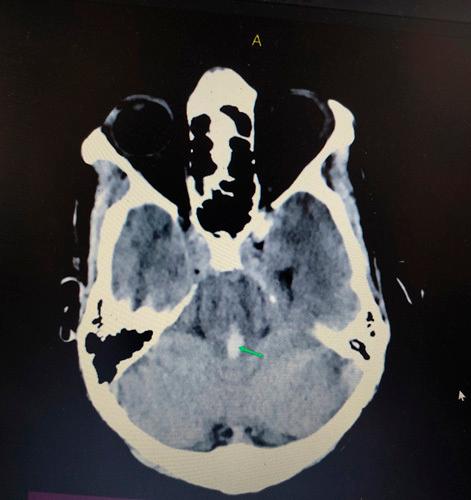

Twenty-three-year-old male with no prior comorbidities presented to emergency with sudden onset loss of consciousness and 1 episode of seizure. No history of intoxication or trauma was given. Glasgow Coma Scale at presentation was E1V2M2. CT scan head revealed bilateral basal ganglia haematoma along intraventricular haemorrhage.

一名23岁无既往合并症的男性因突发意识丧失和1次癫痫发作就诊于急诊科。无中毒或外伤史。就诊时格拉斯哥昏迷量表评分为E1V2M2。头颅CT扫描显示双侧基底节血肿伴脑室内出血。